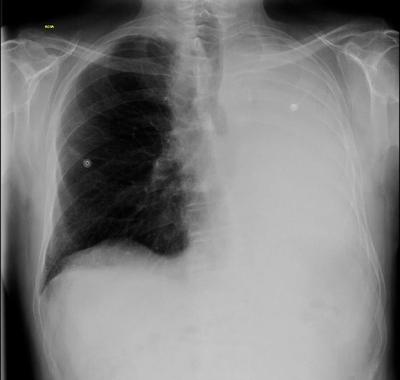

Question 16

Question

patología que se observa en la radiografía.

Answer

• derrame pleural

• atelectasia

• neumotorax